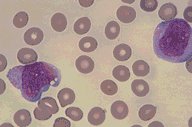

ANLL-M-7

ANLL M7: Wright's stained peripheral blood smear showing two

immature leukemic megakaryoblasts. Other studies were required

to confirm their identity.